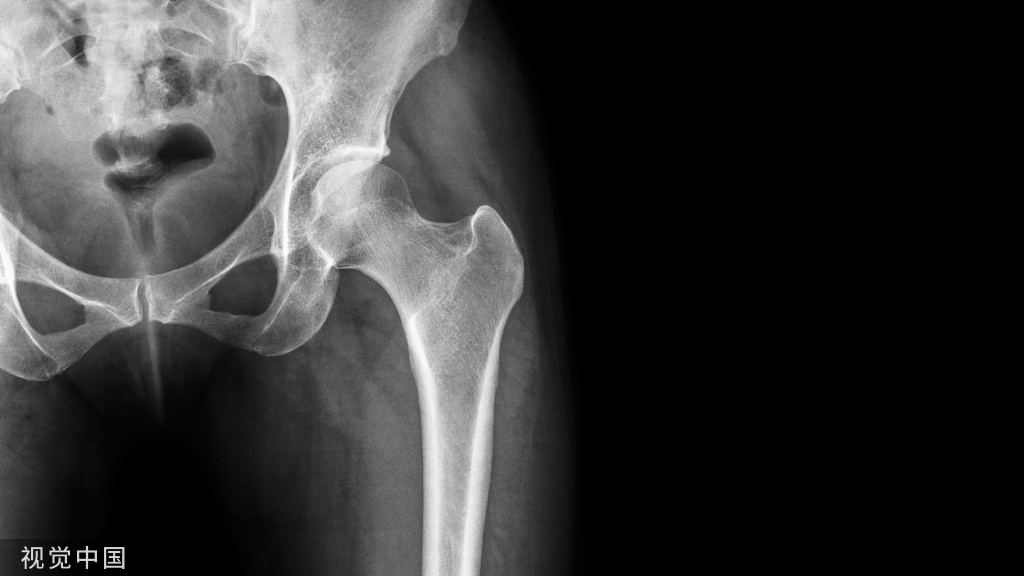

3.带线锚钉治疗髌骨不稳定

髌骨不稳由骨性解剖异常以及软组织限制性不足引起,目前多数学者主张积极手术治疗。

内侧髌股韧带(MPFL)是髌骨静力性稳定机制中最重要的结构,在治疗髌骨不稳的术式中,MPFL重建术是有效的手术方法之一。在MPFL重建技术中,髌骨侧的固定多数采用制作隧道固定,但存在易发生髌骨骨折的缺点。

带线锚钉法:采用髌骨端锚钉固定技术,对于发育不良的小髌骨患者,骨隧道技术极易导致髌骨骨折,锚钉同定技术不侵扰髌骨前方皮质,骨量丢失少,降低髌骨骨折的发生。